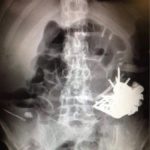

Medicii au extras toate obiectele din stomacul bolnavului, dar după 8 luni, acesta din nou a fost internat în spital, suferind dureri stomacale. De data aceasta a fost nevoie de operație, în urma căreia au fost descoperite unghii, cuie, cuțite, lingurițe, monede chiar și o șurubelniță.

Zilele trecute, bărbatul din nou a fost spitalizat. De această dată, un obiect de metal ce a fost înghițit a spart stomacul ceea ce a provocat o inflamare. La moment, bărbatul se află sub monitorizarea medicilor și a psihiatrilor.